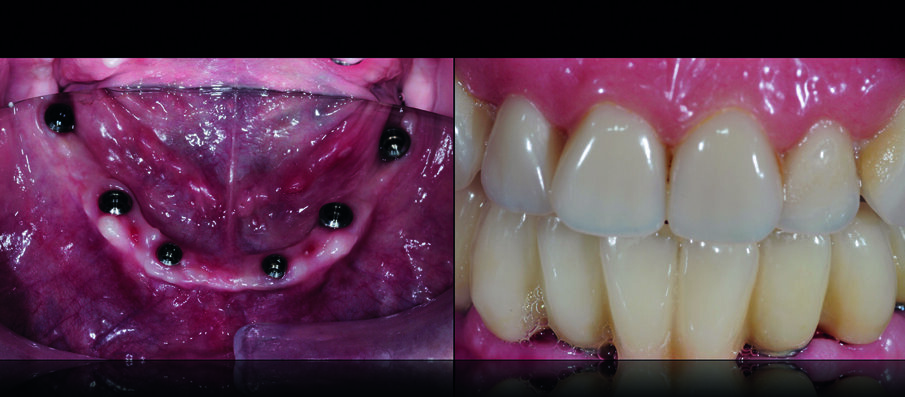

Dopo la loro osteo-integrazione, gli impianti sono stati improntati e, dopo aver registrato la posizione di relazione centrica alla dimensione verticale già testata, è stata verificata la loro posizione utilizzando una placca in resina che ha permesso anche di confermare l’adeguatezza della dimensione verticale di occlusione. Gli ultimi due denti residui sono stati estratti ed è stata consegnata alla paziente una protesi provvisoria fissa inferiore, avvitata sugli impianti (Fig. 10). Nei 30 giorni successivi sono stati valutati funzione, occlusione, fonetica ed estetica e sono state trasferite tutte le informazioni delle protesi provvisorie in quelle definitive. La protesi superiore è stata duplicata e tale replica è stata utilizzata per eseguire l’impronta di precisione del mascellare edentulo (Fig. 11).

La finalizzazione della riabilitazione ha perciò previsto due soluzioni protesiche completamente differenti tra loro: una protesi fissa inferiore avvitata su sei impianti (in metallo-ceramica) ed una protesi rimovibile superiore con denti personalizzati in ceramica presso-fusa) (Figg. 20, 21).

Tali soluzioni hanno permesso di ottenere tutti gli obiettivi prefissati con grande soddisfazione della paziente: ottima funzione in associazione ad una eccellente estetica (Figg. 22, 23).